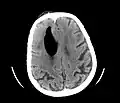

Pneumocephalus has also been shown to follow neurosurgical procedures such as deep brain stimulation and hematoma evacuation (e.g., chronic subdural hematoma[6]), where while seemingly innocuous to the patient, may cause brain shift, subsequent stereotactic inaccuracy, and even another surgical intervention.[7][8] Regarding chronic subdural hematoma (CSDH) surgery, a postoperative volume of pneumocephalus greater than 15mL puts a patient at increased risk of CSDH recurrence; in fact, for every milliliter of air entering the cranial cavity after CSDH evacuation, the recurrence risk increases by 4%.[9] Efforts are made by neurosurgeons to reduce pneumocephalus volume during surgery, and thus, subsequent brain shift.

Additional images

Large pneumocephaly secondary to surgical wound

Pneumocephaly